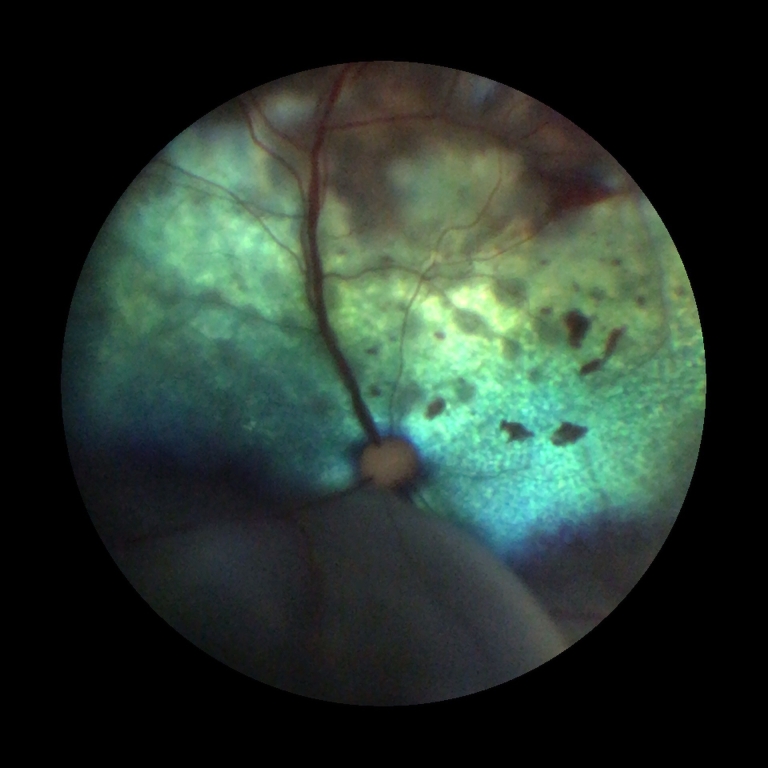

One of the UK’s leading small animal hospitals has added further to its impressive range of state-of-the-art equipment with the arrival of an ultra-modern fundus camera.

A young rabbit can see clearly now after undergoing delicate cataract surgery at one of the UK’s top veterinary clinics.